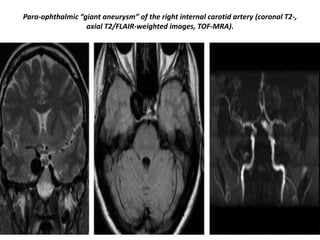

Para-ophthalmic “giant aneurysm” of the right internal carotid artery (coronal T2-,

axial T2/FLAIR-weighted images, TOF-MRA).

Para-ophthalmic “giant aneurysm”of the right internal carotid artery (coronal T2-, axial T2/FLAIR-weighted images, TOF-MRA).